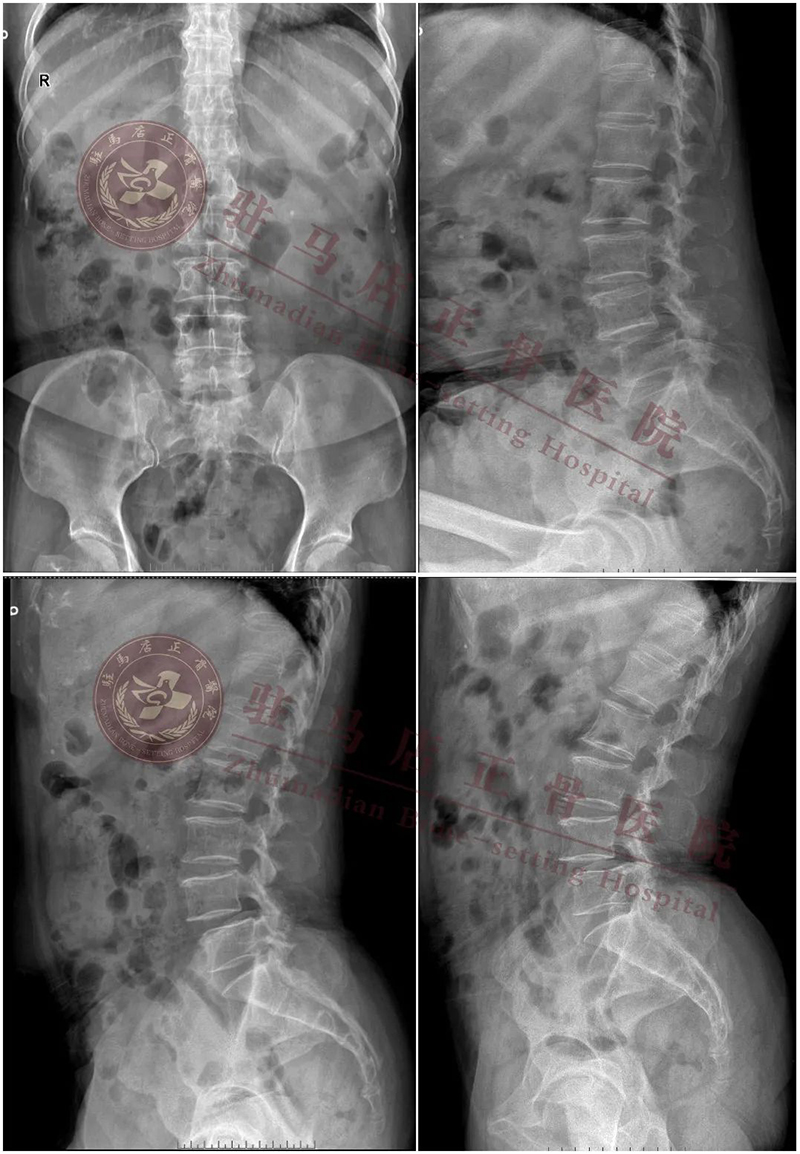

【患者情况】:女性、68岁,职业:农民

【主 诉】:腰痛12年加重伴双下肢疼痛、麻木1年

【诊 断】:1.腰椎管狭窄症(L4/L5); 2.腰椎间盘突出症(L4/L5); 3.腰4椎体滑脱(II度)

【术前计划】:通过影像等相关检查,明确诊断,根据诊断确定手术方式:经内镜下行腰4/5椎间盘切除、椎管扩大减压、椎间植骨融合复位、经皮椎弓根螺钉单侧内固定术

【拟行手术名称】:UBE镜下腰4/5减压融合固定术

{ 术前 }